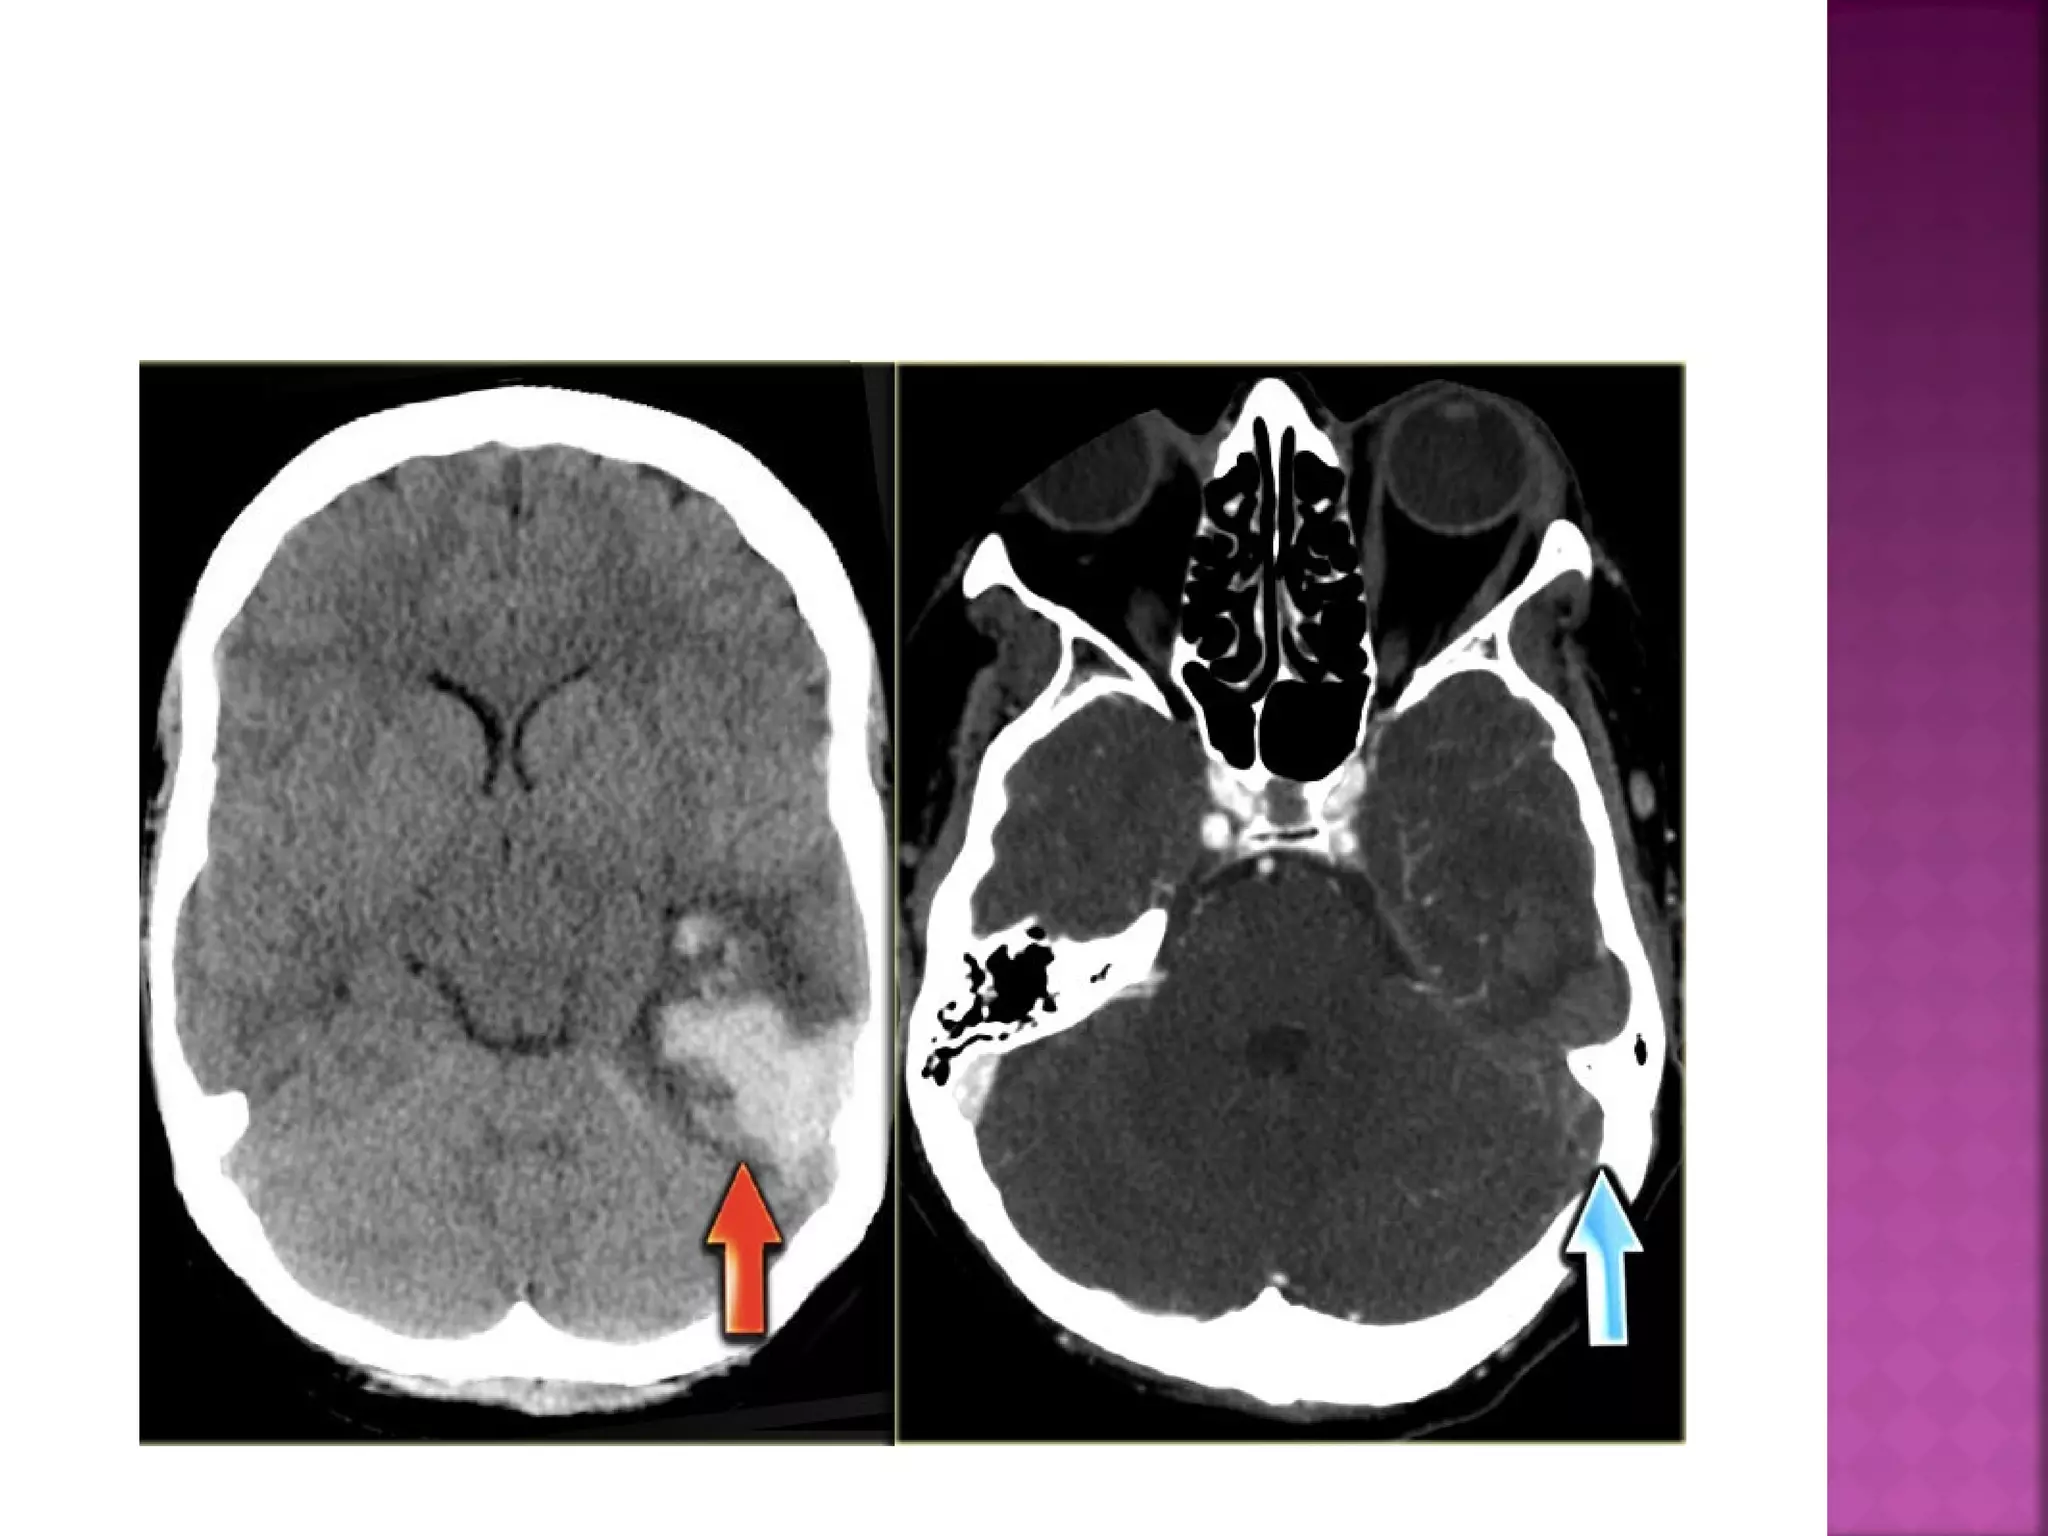

Obscuration of the lentiform nucleus, also

called blurred basal ganglia, is an important

sign of infarction.

It is seen in middle cerebral artery infarction

and is one of the earliest and most

frequently seen signs.

The basal ganglia are almost always involved

in MCA-infarction.

This refers to hypodensity and swelling of the

insular cortex.

It is a very indicative and subtle early CTsign of infarction in the territory of the

middle cerebral artery.

It has to be differentiated from herpes

encephalitis.

This is a result of thrombus or embolus in the

MCA.



 Obscuration of thelentiform nucleus, also called blurred basal ganglia, is an important sign of infarction. It is seen in middle cerebral artery infarction and is one of the earliest and most frequently seen signs. The basal ganglia are almost always involved in MCA-infarction.

 This refers tohypodensity and swelling of the insular cortex. It is a very indicative and subtle early CTsign of infarction in the territory of the middle cerebral artery. It has to be differentiated from herpes encephalitis.

 This is aresult of thrombus or embolus in the MCA.